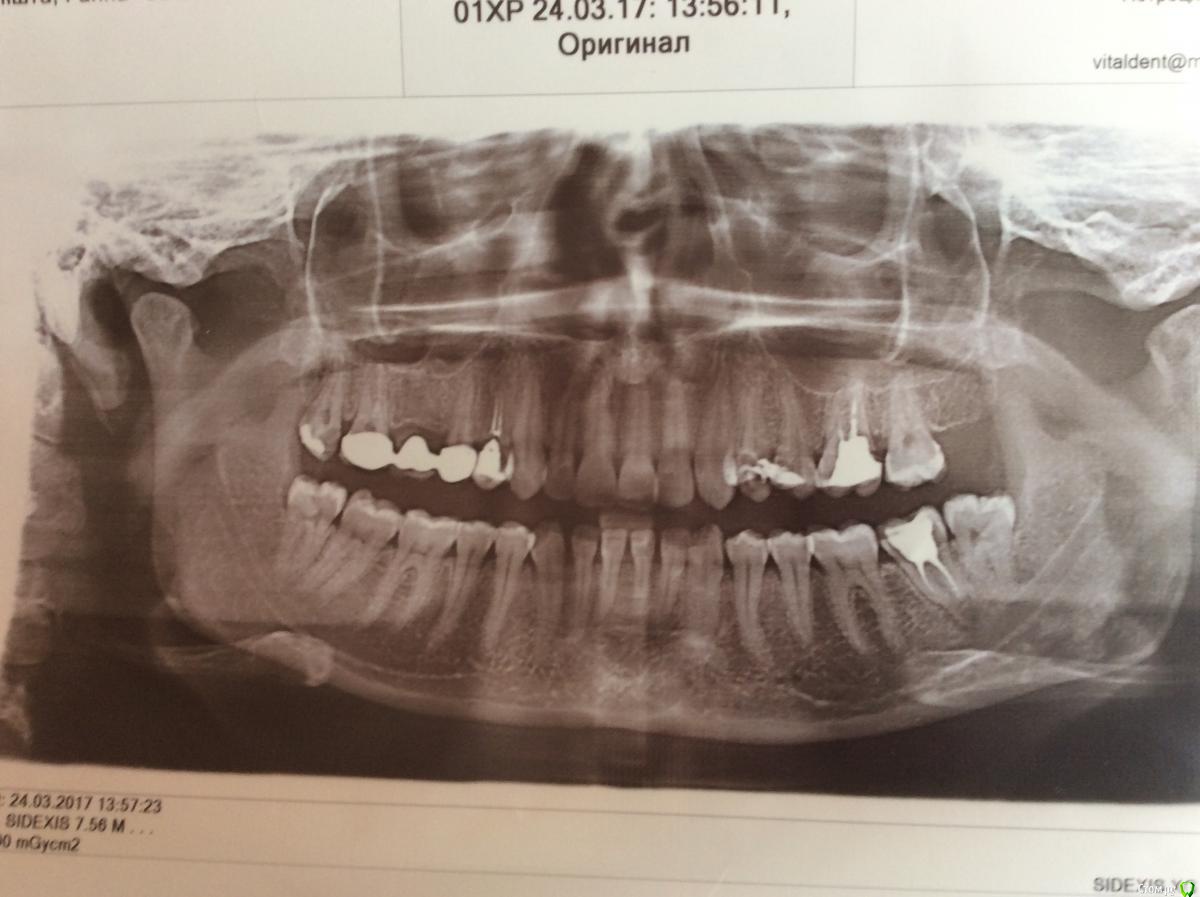

dr.Dre Опубликовано 24 марта, 2017 Поделиться Опубликовано 24 марта, 2017 Добрый день коллеги.Пациентка 26 лет,на 25 зубе гранулёма,была у Лора сказали ити к стоматологу,скажите может быть гайморит от данного зуба? Ссылка на комментарий

Doctor1981 Опубликовано 24 марта, 2017 Поделиться Опубликовано 24 марта, 2017 Может. 24,25 перелечивайте.26-на выход!!! Ссылка на комментарий

Dok22 Опубликовано 24 марта, 2017 Поделиться Опубликовано 24 марта, 2017 Коллеги прекратите порочную практику ставить диагнозы по ОПГ(толко как обзорник) делайте КТ и вперед! 2 Ссылка на комментарий